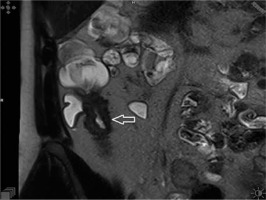

Figure 1

Non-fat saturation T2-weighted coronal image showing significant bowel wall thickening and luminal narrowing of the terminal ileum (arrowhead)